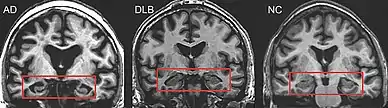

PET or SPECT imaging can be used to detect reduced dopamine transporter uptake and distinguish AD from DLB.[57][149] Severe atrophy of the hippocampus is more typical of AD than DLB.[150] Before dementia develops (during the mild cognitive impairment phase), MRI scans show normal hippocampal volume. After dementia develops, MRI shows more atrophy among individuals with AD, and a slower reduction in volume over time among people with DLB than those with AD.[33] Compared to people with AD, FDG-PET brain scans in people with DLB often show a cingulate island sign.[33]